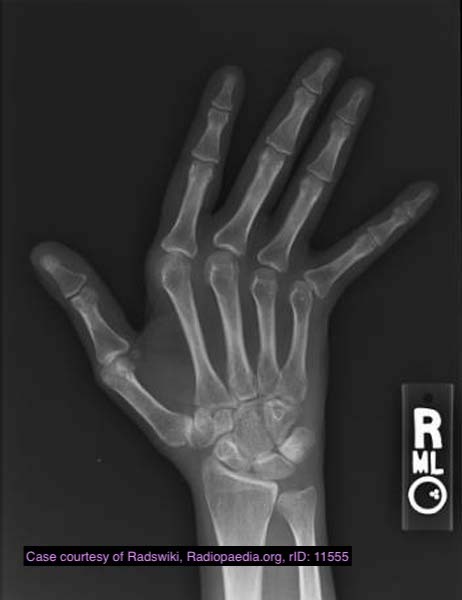

Name this appearance and ddx

Jaccoud arthropathy is a deforming non-erosive arthropathy characterised by ulnar deviation of the second to fifth fingers with metacarpophalangeal joint subluxation.

Clinical presentation

Jaccoud arthropathy is characterised by marked ulnar subluxation and deviation at the metacarpophalangeal joints that is correctable or reducible with physical manipulation 7.

Radiographic features

Plain radiograph

hand radiographs typically show marked ulnar subluxation and deviation at the metacarpophalangeal joints

absence of erosions is a notable feature, although occasionally “hook” erosions may be observed, which are similar to those seen in SLE and ankylosing spondylitis 6

evidence of muscle (soft tissue) atrophy also may be present